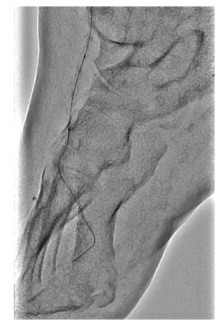

Patients with end-stage foot are commonly diabetic and/or have advanced chronic kidney disease. These patients are at very high risk for major amputation and generally are poor candidates for surgical revascularization due to poor target...